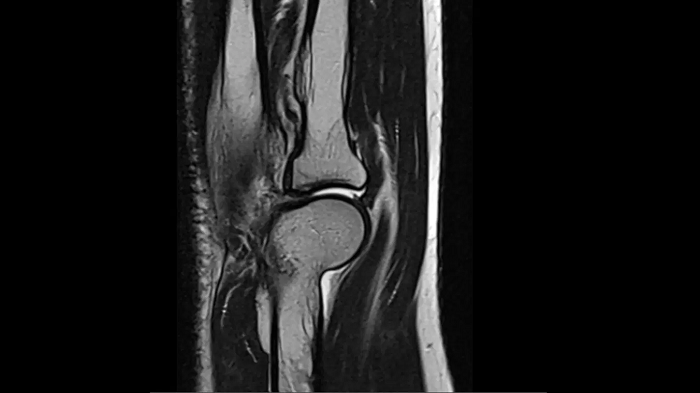

Elbow

T2 TSE with Deep Resolve

Exceptional performance for small joints owing to Deep Resolve.

Deep Resolve Gain & Sharp

0.3 x 0.3 x 3.0 mm2

TA 2:54 minutes

MAC-ID: 7aaaa0190. Image Credit: Siemens Healthineers

T1 TSE with Deep Resolve

Thanks to Simultaneous Multi-Slice and Deep Resolve, an exceptional performance for small joints is possible.

SMS 2 | Deep Resolve Gain & Sharp

TA 2:15 minutes